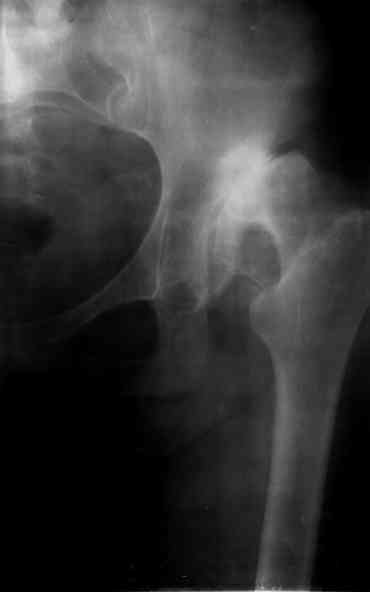

Ув. коллеги, женщина, 37 лет, имеет диспластический коксартроз. Сомневается в положительном результате от эндопротезирования, но хочет оперироваться. Что порекомендуете? С ув. Sergey A. Melashenko ул. Кирова 88-А, г. Приморск, Запорожская обл., 72100, Украина

Оперироваться. Альтернативы нет. Надо делать обе ноги, поочередно с реконструкцией крыш для последующей удобной ревизии. Ножки бесцементные.

Сергей. Операция первичного эндопротезирования предусматривает у данной больной (я бы сделал так) - 1. Доступ с хорошим обзором впадины (или задний

или с пересечением б.вертела) - затем установку тазового компонента с одномоментной пластикой крыши вертлужной впадины из утилизируемой головки

(если получится бесцементная чаша - это лучше, но не факт - вероятно будет моделирующее кольцо с цементируемой чашей - внимание к "версии" чаши) -

затем классическая бесцементная ножка. Справа будет попроще. Слева рассчет после установки правого сустава. Может потребоваться двухэтапное

протезирование. При отсутствии проблем с финансировании - отправьта в Харьков - Киев - Донецк. С уважением. А Рыков.

1. при таком анатомическом варианте корригирующие остеотомии явно проигрывают тотальному эндопротезированию.

2. первым этапом оперируем сторону с преобладающим болевым.

3. справа может быть будет достаточно структурного аутотрансплантата, но вариант с кольцом надо иметь в виду; слева использовал бы армирующую конструкцию (плохая надацетабулярная кость - проблемное приживление трансплантата).

4. вероятность осложнений выше, чем в банальной ситуации, правильно дама беспокоится, лучше делать операцию там, где это на потоке. Если ближе не найдется, присылайте.